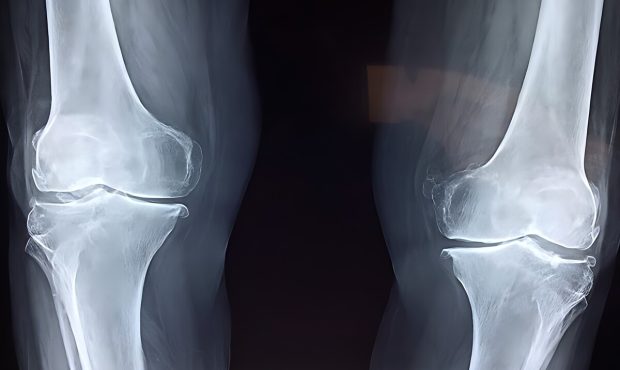

آسیب به استخوانها

نخستین نگرانی، تاثیر منفی بر سلامت استخوانهاست. مصرف نوشابه و الکل هر دو با کاهش تراکم مواد معدنی استخوان و افزایش خطر شکستگی مرتبط است. مصرف نوشابه بهدلیل وجود اسید فسفریک میتواند تعادل کلسیم و فسفر را بر هم بزند و خطر شکستگی لگن را افزایش دهد. مصرف الکل نیز با کمبود کلسیم، اختلالهای کبدی و کاهش ویتامین دی همراه است که همگی به تضعیف استخوانها منجر میشوند.